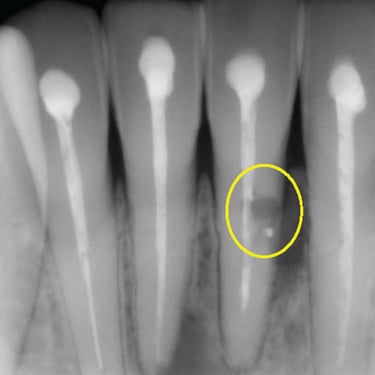

Calcificación Pulpar

La calcificación pulpar es la formación de depósitos de calcio dentro de la pulpa dental, que puede dificultar el tratamiento de conducto.

Los pacientes generalmente no tienen síntomas, pero pueden experimentar sensibilidad.

El tratamiento incluye la eliminación de los depósitos durante el tratamiento de conducto. Es importante tratarlo para evitar complicaciones durante el procedimiento.